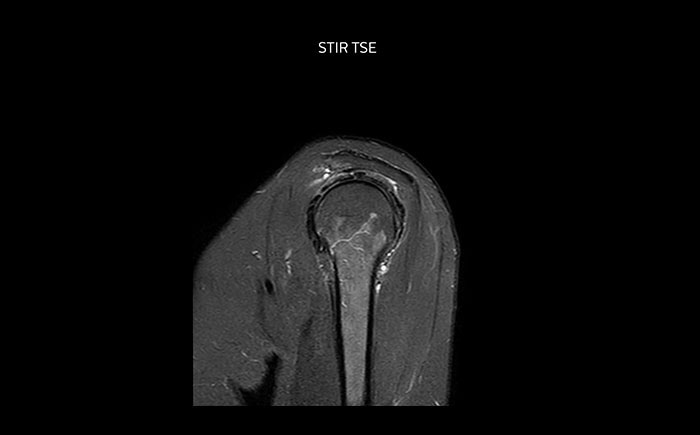

The Prodiva shoulder coil is very flexible and has large coverage, which makes good positioning easier, and that contributes to the superb image quality and high SNR that we get in our shoulder exams.

Scan time 2:55 min, FOV 160 mm, acq voxels 0.55 x 0.83 x 3.0 mm.

Scan time 4:19 min, FOV 160 mm, acq voxels 0.55 x 0.80 x 3.0 mm.

Scan time 2:50 min, FOV 160 mm, acq voxels 0.70 x 0.99 x 3.0 mm.